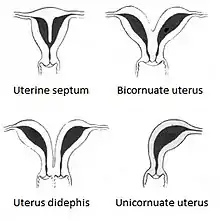

A bicornuate uterus or bicornate uterus (from the Latin cornū, meaning "horn"), is a type of mullerian anomaly in the human uterus, where there is a deep indentation at the fundus (top) of the uterus.

A bicornuate uterus develops during embryogenesis. It occurs when the proximal (upper) portion of the paramesonephric ducts does not fuse, but the distal portion that develops into the lower uterine segment, cervix, and upper vagina fuses normally.[1]

Bicornuate uterus is typically classified based on whether or not the division extends to the external cervical os. Bicornuate uteri with a division above the os are called bicornuate unicollis and those with a divided os are called bicornuate bicollis.[2] There is a continuous range of the degree and location of the fusion of the paramesonephric ducts, and existence of a spectrum, rather than a fixed number of types corresponding to strict medical definitions. Two processes that occur during the embryonic development of the paramesonephric ducts — fusion and reabsorption — can be affected to different degrees.[3]